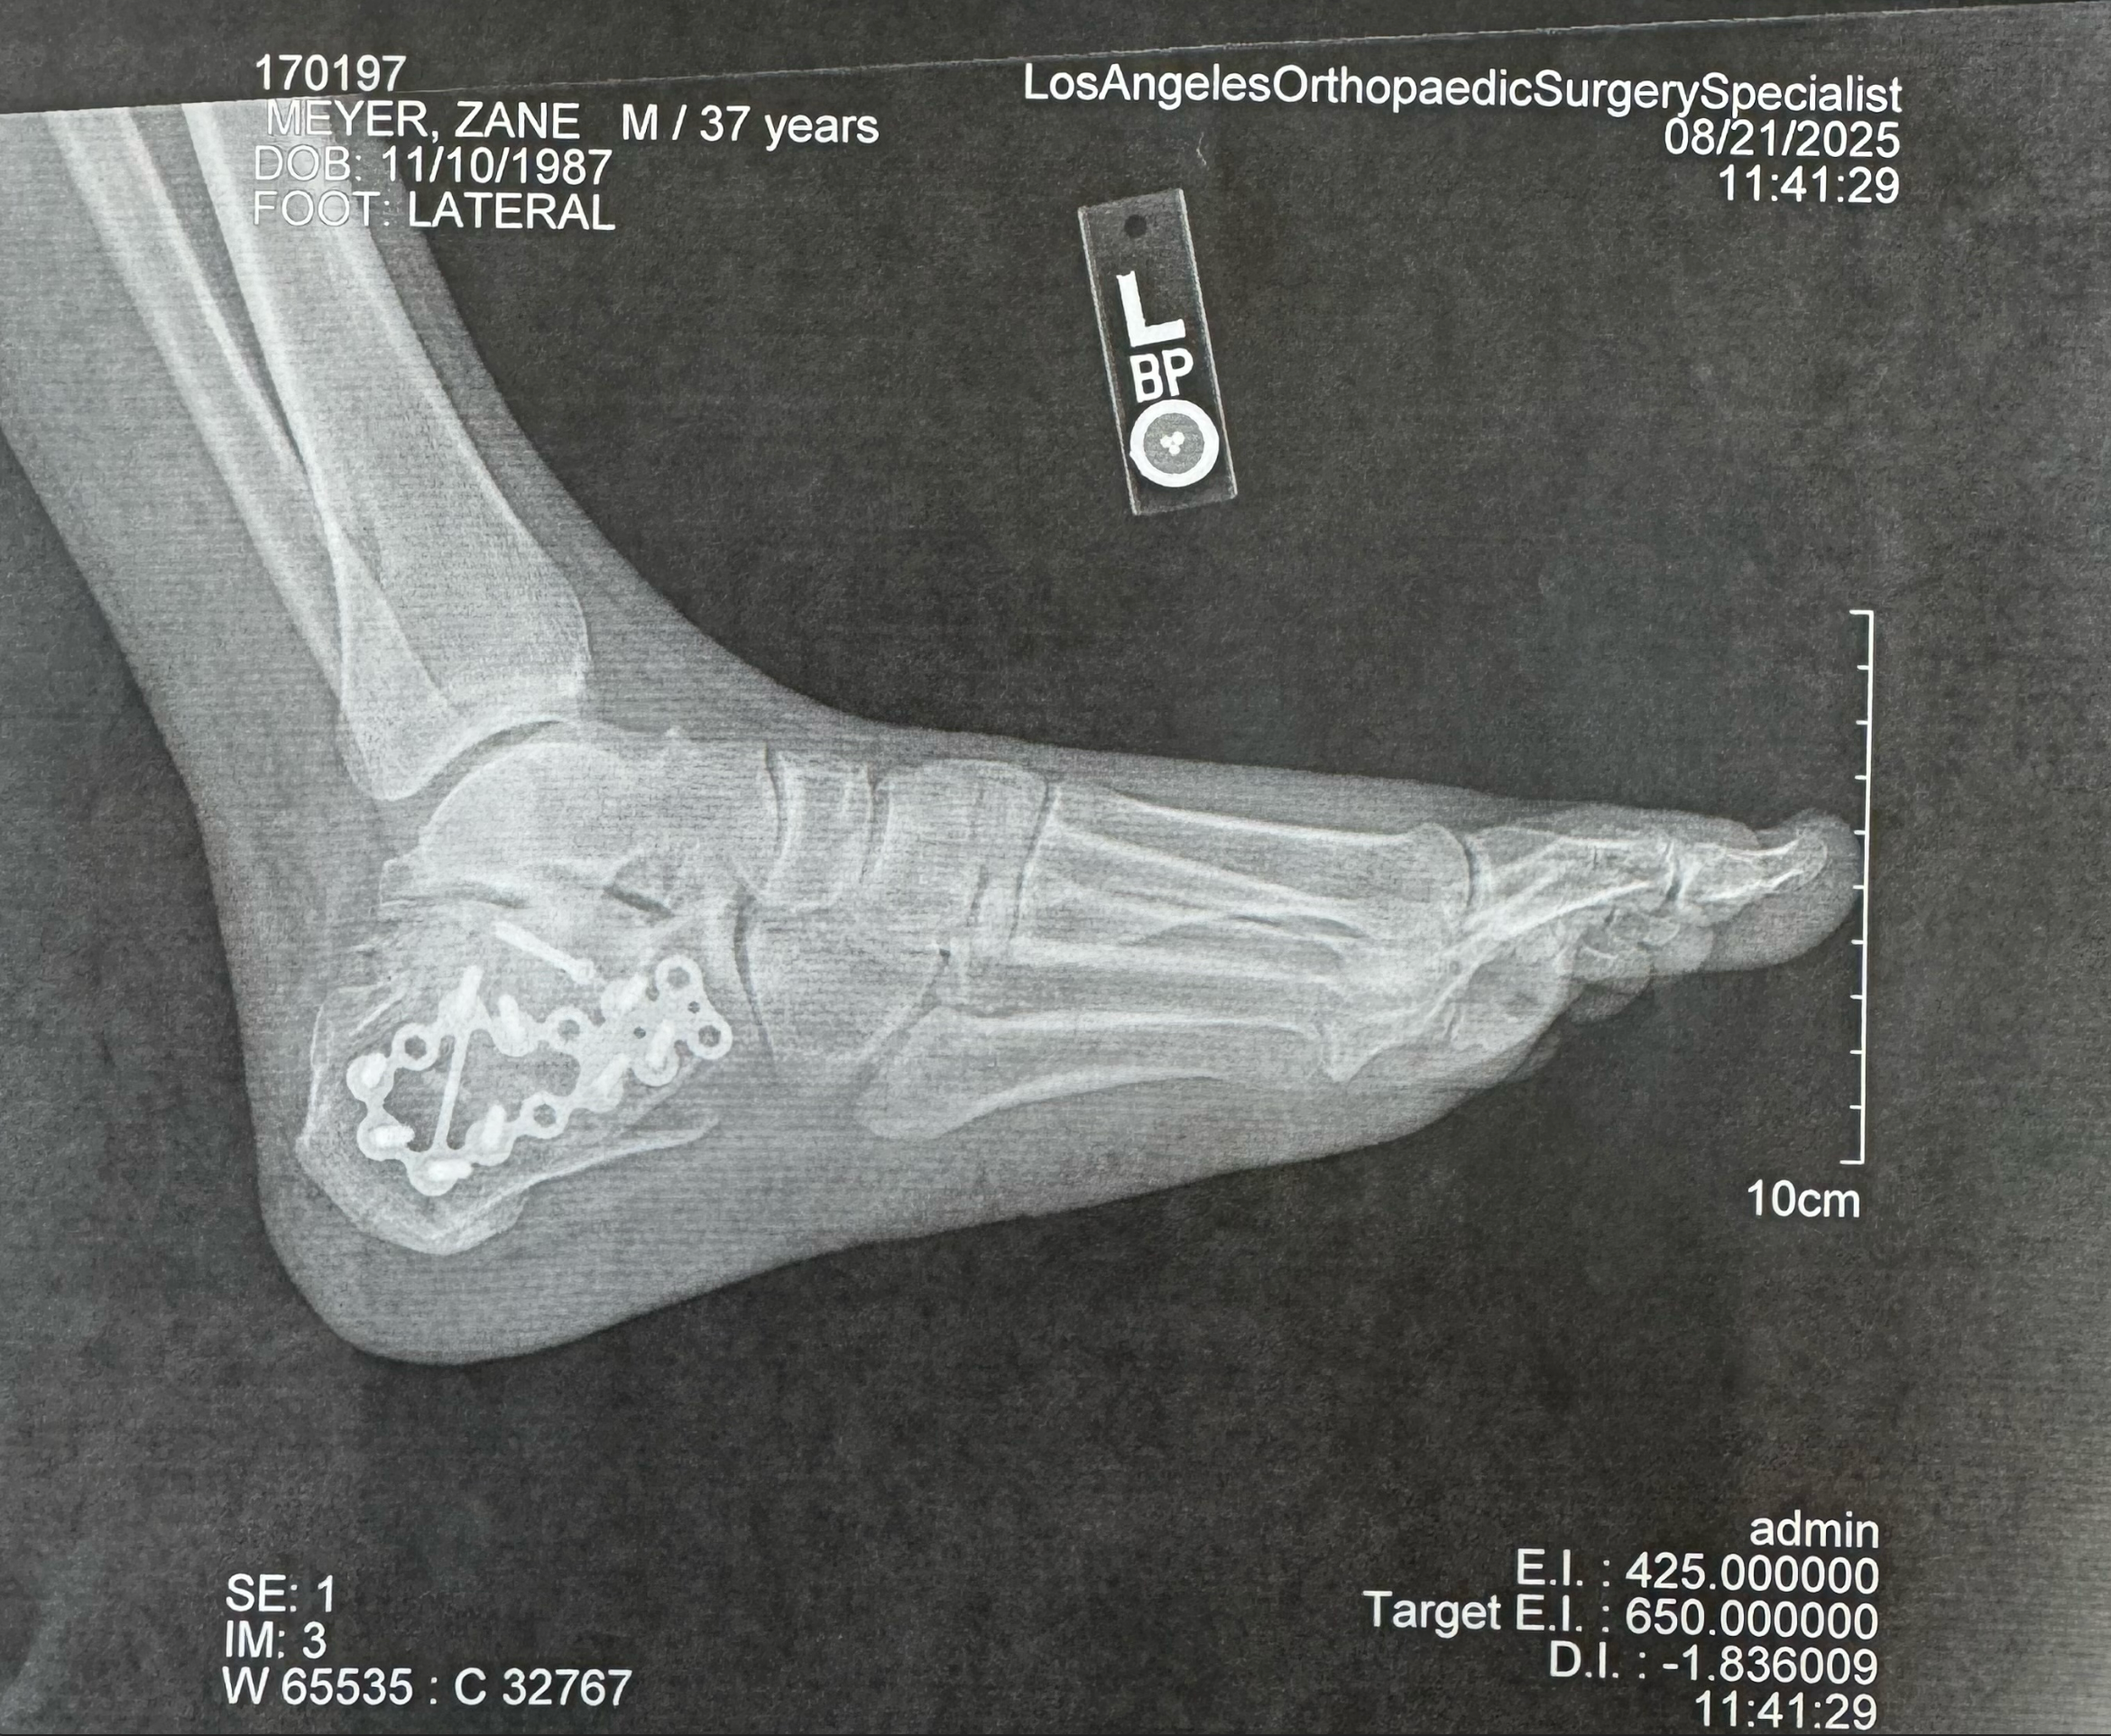

Last month, I suffered a devastating accident that shattered my heel and left me in debilitating pain and unable to work. The injury was so severe it required intensive surgery and I now face a long road to recovery. My doctor told me I’ll never walk the same again. I’ll be dealing with chronic pain and a bone fusion surgery is likely within the next 1–3 years. On top of that, my insurance had lapsed, so every medical bill has been out of pocket.